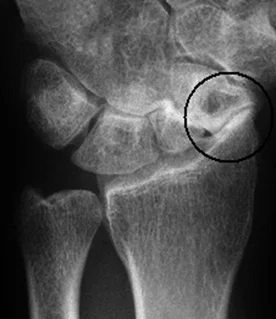

Scaphoid Fracture

- Scaphoid is the common fractured carpal bone

- Fall on the palm of the outstretched hand

- Presents with pain, tenderness in the anatomical snuffbox

- Radiology:

- AP and Lateral not enough

- Need an special scaphoid view

- Complications

- Avascular necrosis (AVN):

- Mainly proximal 1/3 fracture

- Non-union:

- In undiagnosed or undertreated scaphoid#

- Wrist osteoarthritis

- A result of non-union and AVN

narrowing+ sclerosis